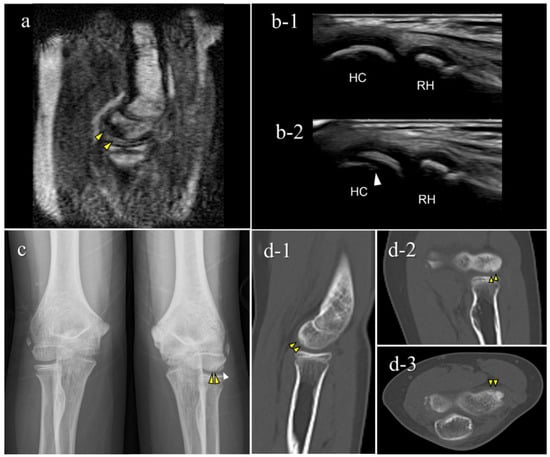

Figure 7. An OCD case during the healing process (Case 5): Mobile MRI (+), US (-). (a) Mobile MR image of T1WI sagittal: Mobile MRI showing signal intensity changes reflecting bone marrow edema in the anterior humeral capitellum; (b) US image of the posterior longitudinal view: b-1, the central posterior; b-2, the lateral posterior: US images showing no significant findings in the central posterior longitudinal view. However, there was a subchondral bone discontinuity in the lateral posterior longitudinal view; (c) X-p AP view with elbow 45° flexed: X-p 45° showing delayed ossification in the lateral capitellum, observed in incomplete healing OCD cases []. In addition, there was a translucent area in the central capitellum, stage I-OCD; (d) CT images: d-1, sagittal image; d-2, coronal image; d-3, axial image: CT images showing the subchondral bone sclerosis, and the surface was almost repaired. White arrowheads: delayed ossification.